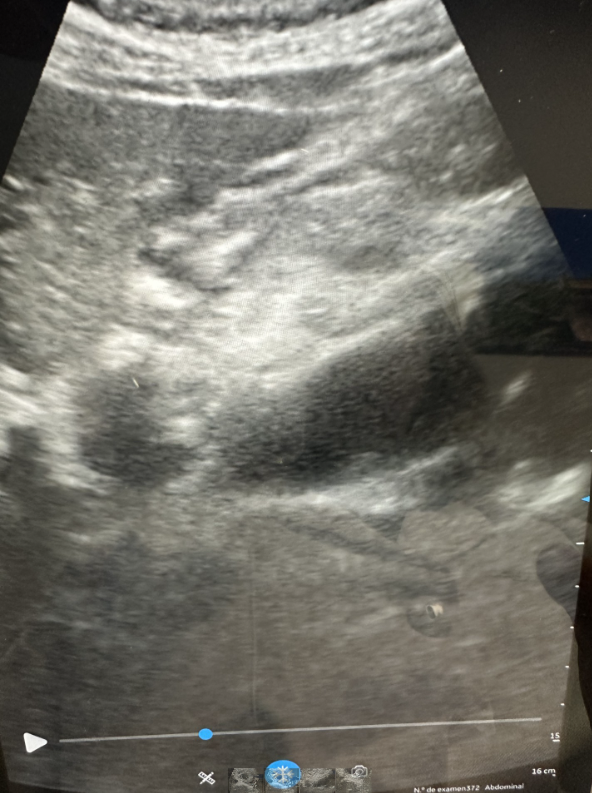

La ecografía clínica realizada en nuestra consulta de Atención Primaria mostró un aneurisma de aorta infrarrenal de 5,3 × 8,1 cm, con trombo intramural y sospecha de disección, hallazgo no presente en estudios previos.

No fue posible completar un angio-TAC urgente, ya que el paciente rechazó acudir a Urgencias pese a la información sobre riesgo vital. Considerando el estudio de 2024 y los hallazgos ecográficos actuales, podía esperarse progresión aneurismática con mayor irregularidad mural y posible disección crónica, sin poder confirmar complicación aguda.